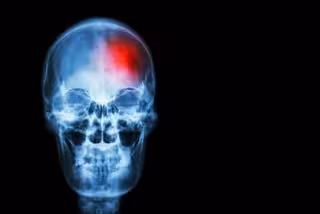

Archivo - Ictus

Archivo - Ictus - STOCKDEVIL/ ICTUS - Archivo